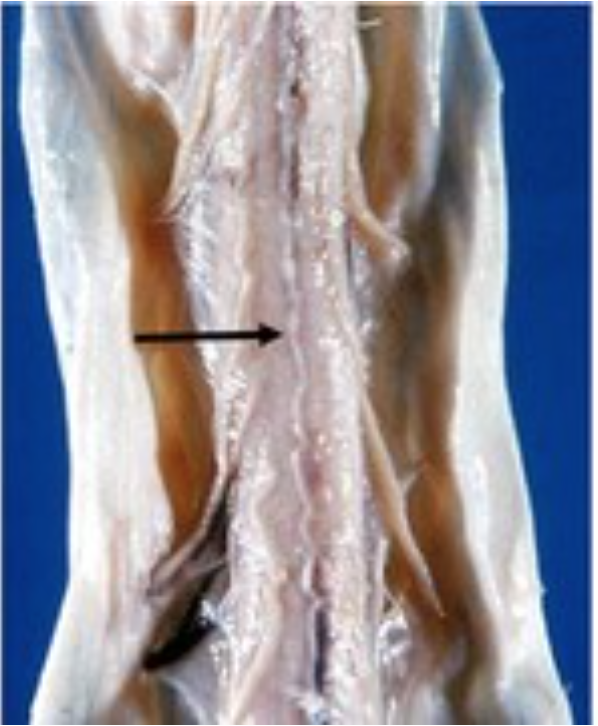

Identify “1”

conus medullaris

Identify 2

filum terminae